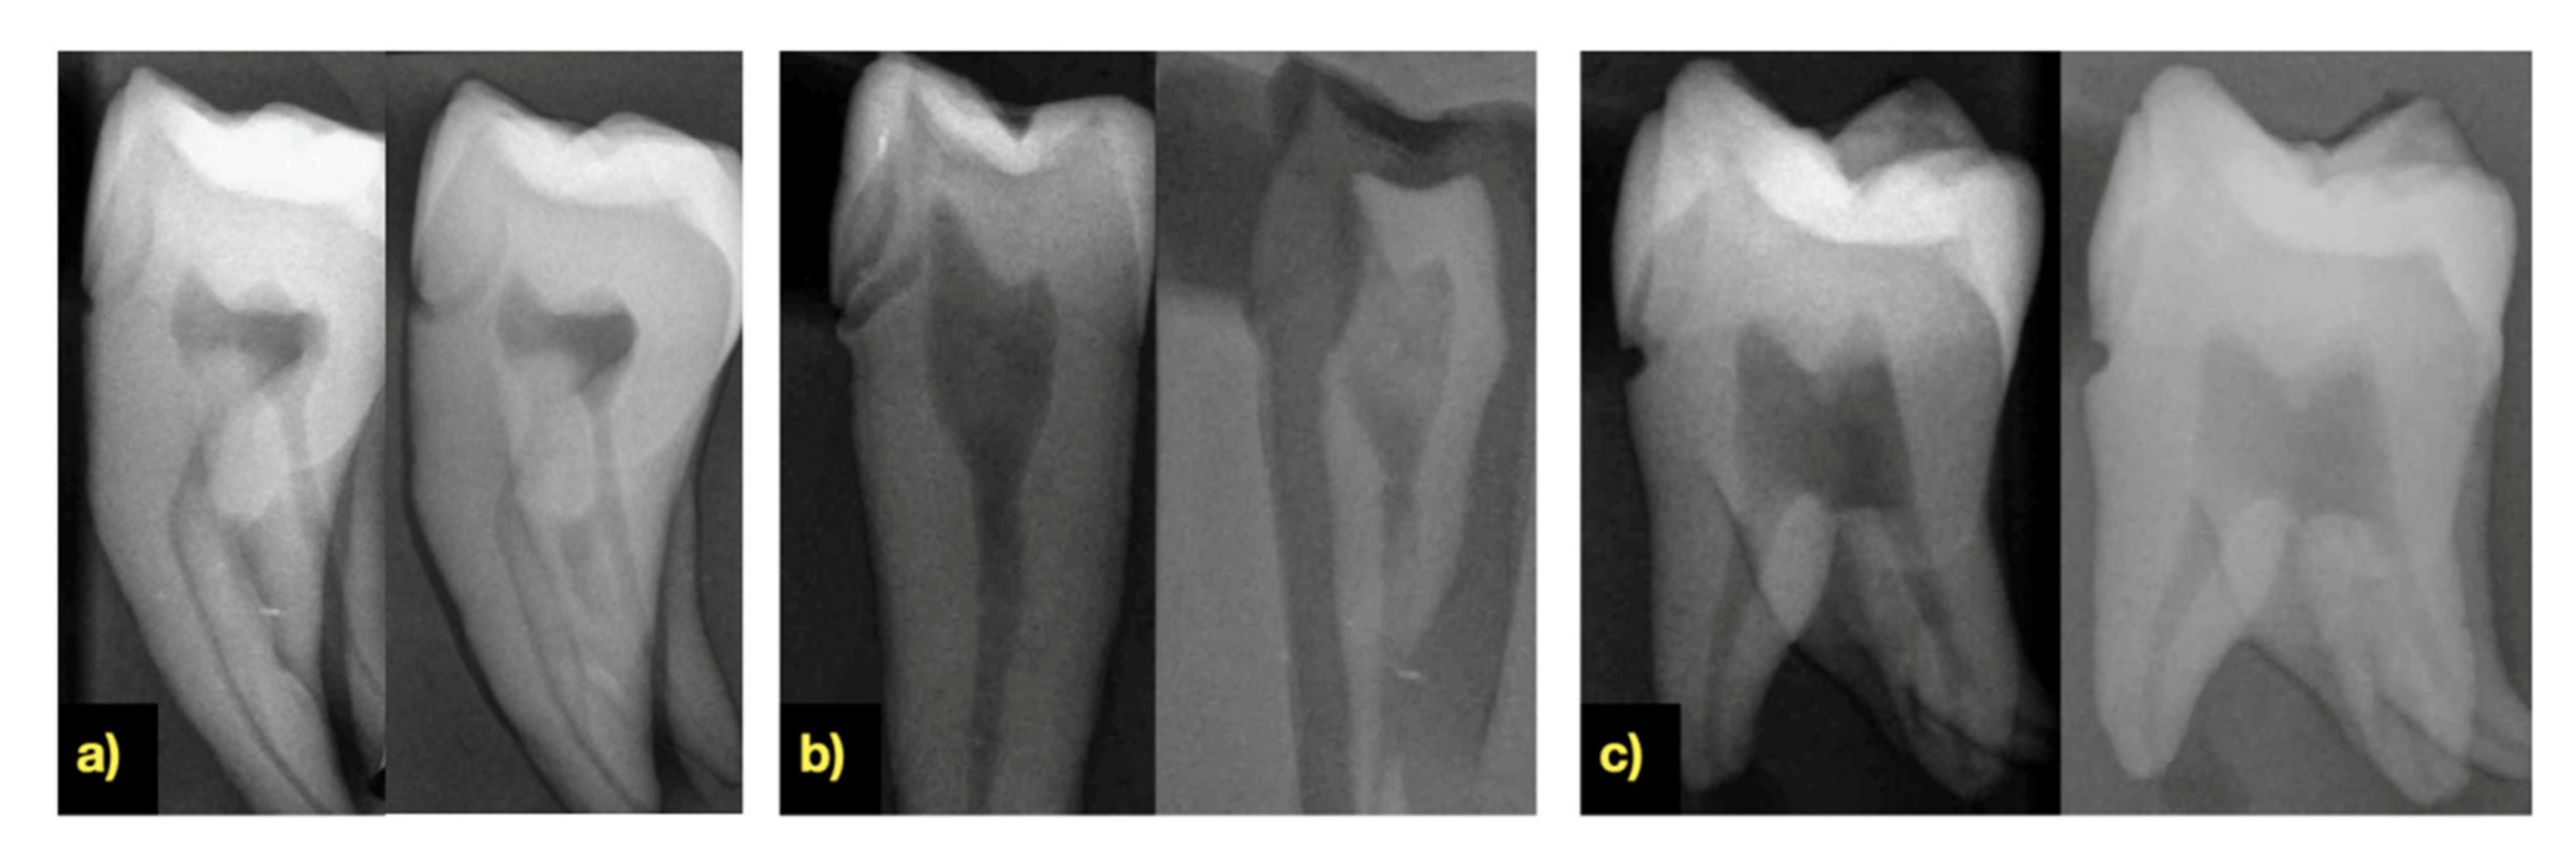

3.5. X-ray